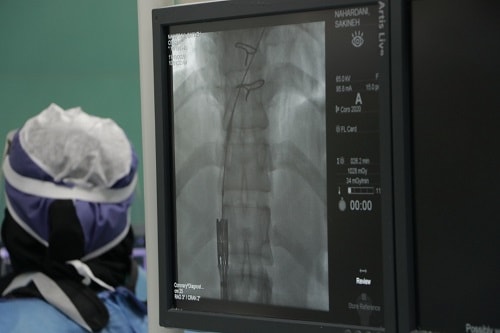

استاد گروه قلب و عروق دانشگاه علوم پزشکی مشهد در گفتگو با وب دا اظهار کرد: این عمل بر روی یک خانم 38 ساله ویک آقای 36 ساله که پیش از این تحت عمل جراحی باز تعویض دریچه قلب قرار گرفته بودند و پس از گذشت چند سال دچار مشکل شده بودند و با توجه به ریسک بالا امکان عمل جراحی باز مجدد وجود نداشت ، به روش آنژیوگرافی انجام شد.

دکتر محمود شبستری ضمن قدردانی از همراهی و همکاری دکتر حاج زینعلی از اساتید قلب وعروق دانشگاه تهران افزود : در این روش همان دریچه قلبی بافتی از طریق پوست مانند آنژیوگرافی ساده وارد قلب می شود و بر روی دریچه قبلی که دچار اشکال شده بوده کارگذاری می شود.

این عمل پیشرفته با همکاری و مشارکت دکتر محمودشبستری، دکترحاج زینعلی،دکتر محمد عباسی ، اساتید گروه بیهوشی و کادر مراقبت و درمان اتاق عمل آنژیوگرافی ساختمان 610 تختخوابی بیمارستان امام رضا(ع) با موفقیت انجام شد.